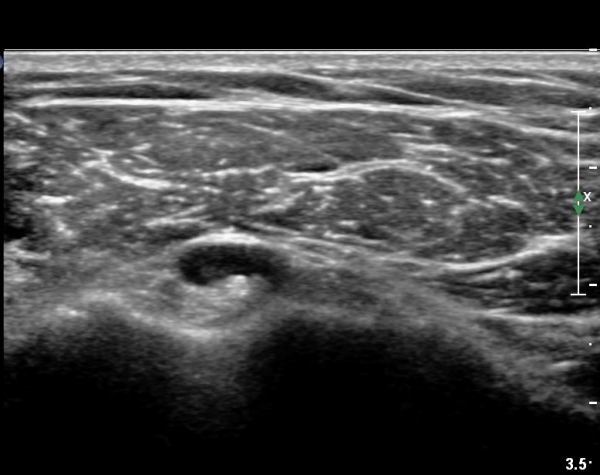

°ß°©ÇϱٰǠ Á¾´Ü¸é°Ë»ç¿¡¼­ °ÇºÎÂøºÎ¿¡ ÀÛÀº ¼®È¸È­À½¿µÀÌ °üÂûµÊ(»çÁø 2).